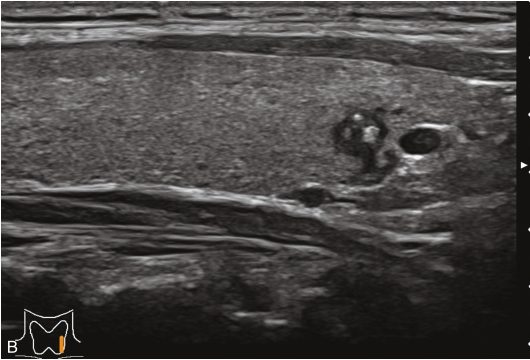

患者71岁女性,因“发现甲状腺包块1.5年,颈部疼痛5个月”入院。5个月前间断出现吞咽后梗阻,颈部疼痛。

图像描述:右叶中下部见一等回声结节,边界清,形态规则,周边见低回声晕,内回声欠均;结节内见较丰富点条状血流信号,周边见环状血流信号,见图1-3-24。

图像描述:甲状腺右叶中下部结节早于周围腺体组织增强,达峰后呈不均匀高增强,周边见高增强环,消退与周围腺体组织同步,仍呈稍高增强,见图1-3-25。

甲状腺嗜酸细胞腺瘤超声造影与其他腺瘤表现基本一致,呈膨胀性生长,包膜完整。因供应其生长的动静脉被增大的瘤体挤压至周边形成丰富的包绕血管,并向内部逐级发出分支。因此超声造影常从周边开始向内部不均匀增强,可见周边环状增强,内部轻度增强或等增强,强度小于周边,达峰时结节整体呈高增强,而廓清时结节通常晚于相邻甲状腺实质呈缓慢消退。

图1-3-24 甲状腺嗜酸性细胞腺瘤常规超声声像图

A.甲状腺右叶等回声结节纵切面灰阶超声图像;B.甲状腺右叶等回声结节CDFI图像

图1-3-25 甲状腺嗜酸性细胞腺瘤超声造影图

A.甲状腺结节造影后12s图像;B.甲状腺结节造影后16s图像;C.甲状腺结节造影后30s图像